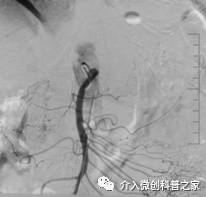

中晚期胰腺癌侵及十二指肠行十二指肠支架植入治疗

(解除肠道梗阻保持通畅)